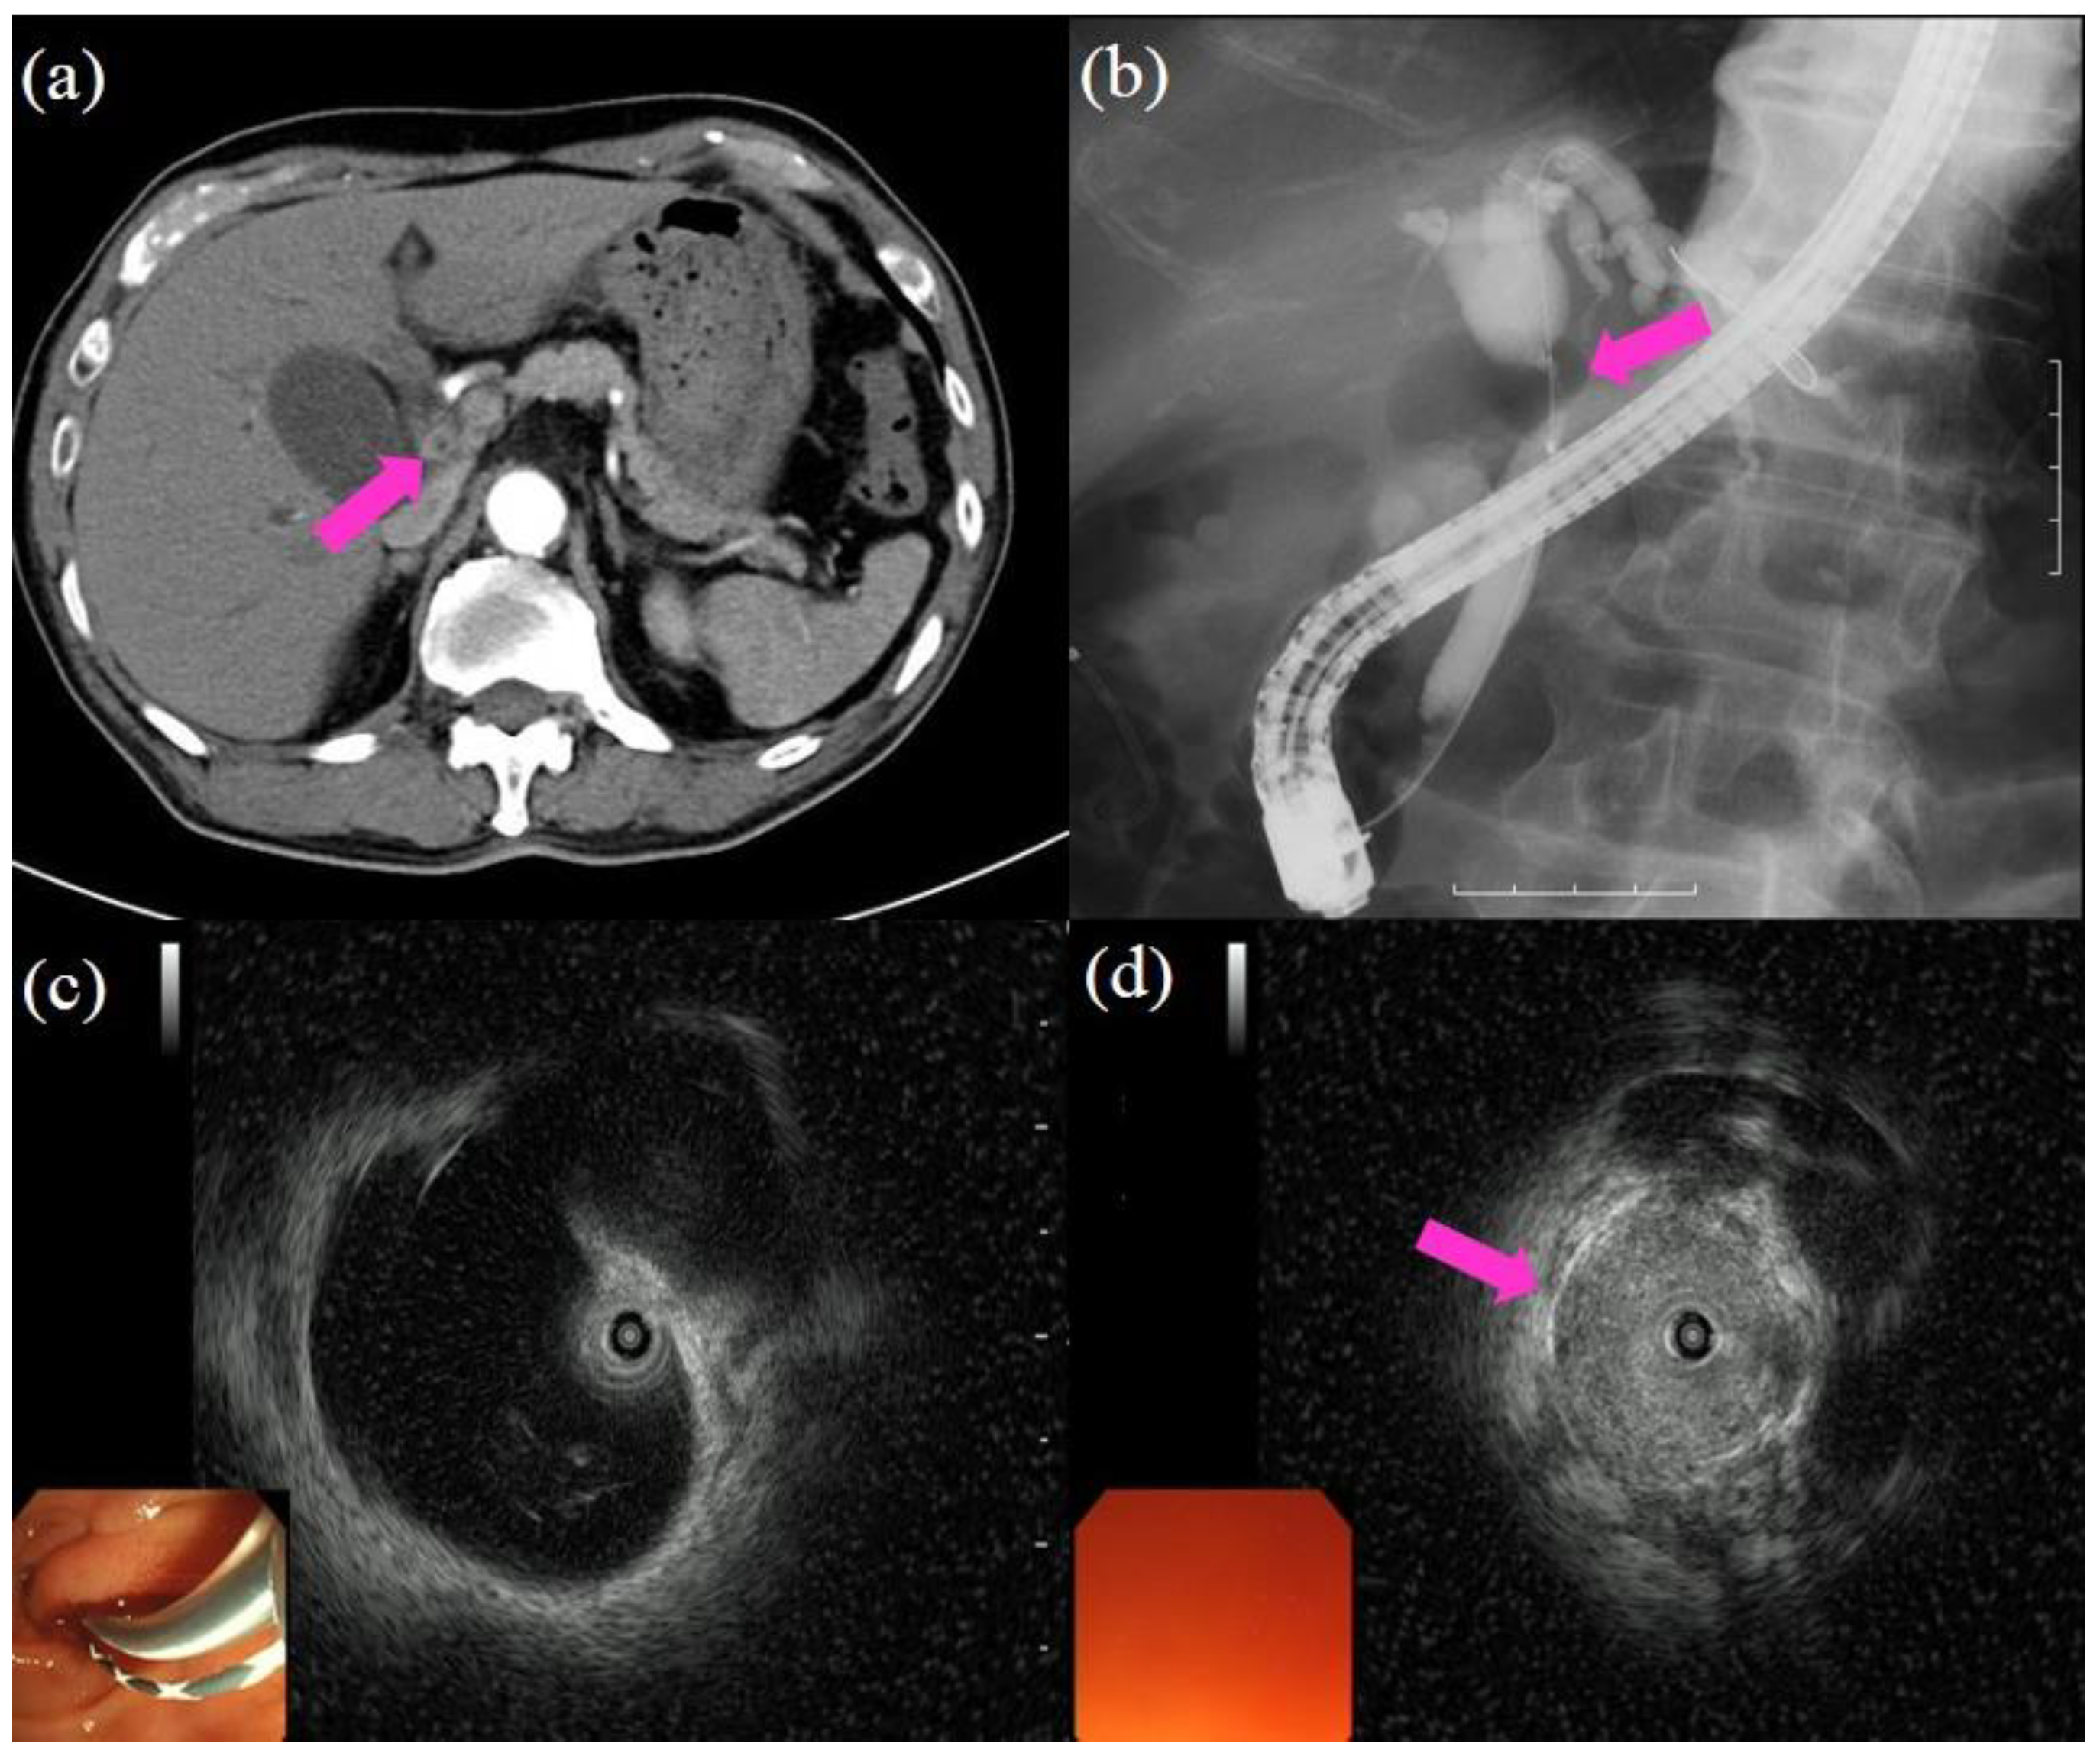

- Sun, B.; Hu, B. The role of intraductal ultrasonography in pancreatobiliary diseases. Endosc. Ultrasound 2016, 5, 291–299. [Google Scholar] [CrossRef]

- Meister, T.; Heinzow, H.S.; Woestmeyer, C.; Lenz, P.; Menzel, J.; Kucharzik, T.; Domschke, W.; Domagk, D. Intraductal ultrasound substantiates diagnostics of bile duct strictures of uncertain etiology. World J. Gastroenterol. 2013, 19, 874–881. [Google Scholar] [CrossRef]

- Tanisaka, Y.; Ryozawa, S.; Nonaka, K.; Yasuda, M.; Fujita, A.; Ogawa, T.; Mizuide, M.; Tashima, T.; Araki, R. Diagnosis of Biliary Strictures Using Probe-Based Confocal Laser Endomicroscopy under the Direct View of Peroral Cholangioscopy: Results of a Prospective Study (with Video). Gastroenterol. Res. Pract. 2020, 2020, 1–9. [Google Scholar] [CrossRef]